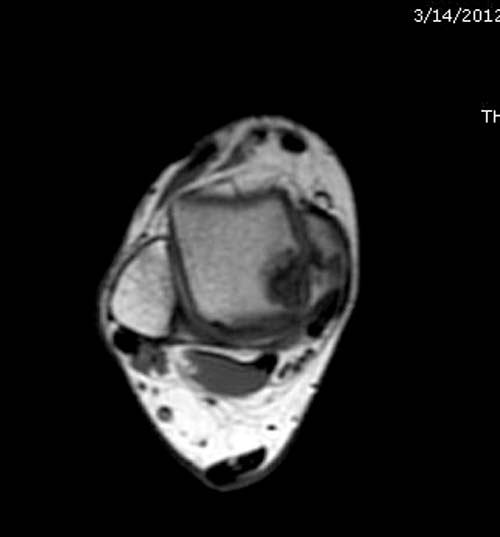

Разбираемый случай не имеет ничего общего с классическим Аваскулярным Некрозом Таранной кости. Здесь так назывемый (osteochondral defect) или osteochondritis dissecans (OCD) таранной кости, при котором патология локализуется в медиально-верхнем нагрузочном отделе. В основном OCD

на рентгенограммах не всегда заметны склерозные участки, и поэтому в большинстве диагноз устанавливается поздно. Приход КТ и МРТ улучшил диагностику, и в срезах внутри кисты можно увидеть жидкость, но это не означает проявление симптоматологии. Симптомы проявляются с момента образования внутрисуставных краевых фрагментаций!

Артроскопия с дебридментом приносит облегчение, но огромные медиально-верхние дефекты надо замещать. Хирургический доступ через медиальную лодыжку, а для замещения применяют современные алломатериалы.

Для ресторации хряща используем хорошо зарекомендовавший продукт компании DeNovo, который полностью восстанавливает повреждение.

И пару дней назад провели операцию... А при огромных дефектах остеохондральный аллографт который выбирается по контуру тарана.